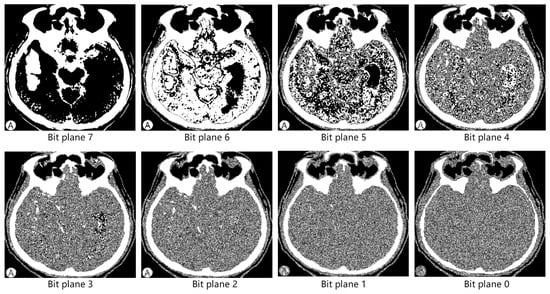

For example, the binary representation of a pixel value of 206 is 11001110, which has a value of one in Bit Plane 7, one in Bit Plane 6, …, and zero in Bit Plane 0. P performs a bit plane decomposition into eight binary bit planes , each bit plane is formed by the ith bit of all pixels in the image. To visualize the information distribution in each bit plane more intuitively, we chose a CT image of the brain and decomposed it into 8-bit planes. Figure 2 shows the image information contained in each bit plane from high to low. It can be visualized that the high-bit planes hold a majority of the contour and structural information. The low-bit plane is barely visible as edges and contours and contains more detail and noise. The properties of the bit plane have led to extensive applications across multiple image processing domains. In image compression, image size can be reduced by selective compression based on the importance of the bit planes [31]. In image enhancement, the processing of the special localization plane allows targeted adjustment of the contrast, brightness, and other features of the image [32]. In image encryption, the transformation of specific bit planes enables secure protection of the image content by encrypting the pixel values within those planes using advanced cryptographic algorithms [33]. In digital watermarking, by selecting appropriate positions and methods to embed watermark information in bit planes, the function of copyright protection can be achieved without interfering with the normal visual effects of the image [34]. Usually, the lower bit planes are chosen to embed watermarks because the slight changes in the lower bit planes have no significant impact on the visual quality of the image. Overall, the analysis of the bit plane helps to deeply understand the inner structure of the image, providing new perspectives and methods for image processing.

Figure 2.

Bit-plane decomposition of the brain CT image.